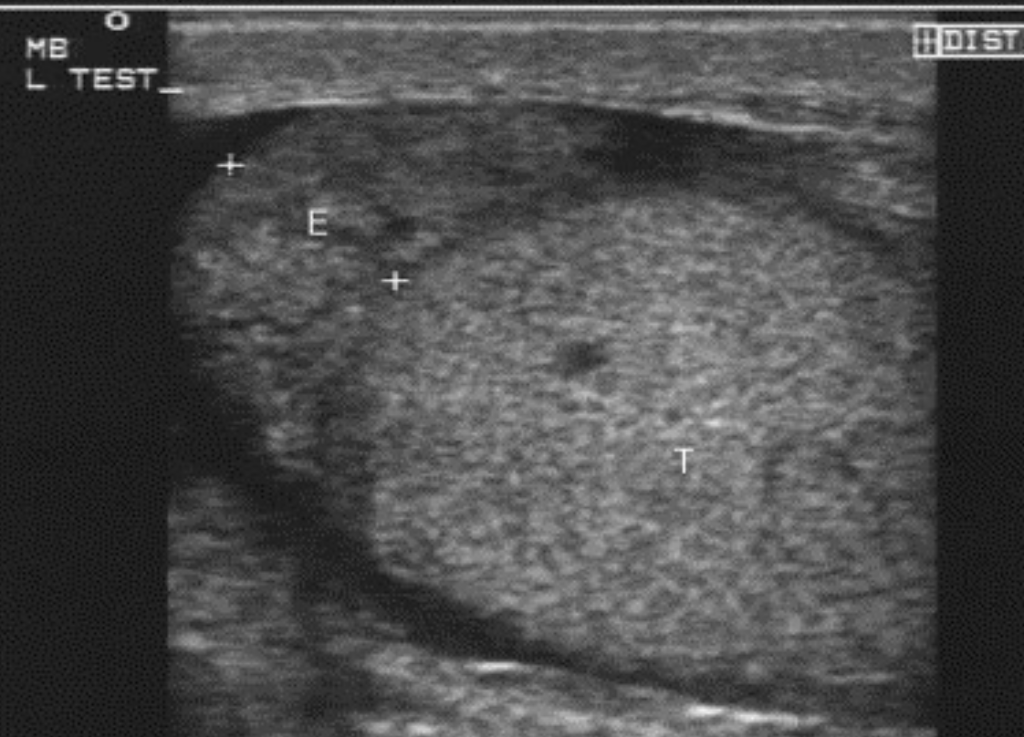

Epididymitis, shown by enlargement of the epididymal head (E). Source: Blaivas & Brannam, 2004.

- Findings: In epididymitis, there is typically enlargement of the epididymal head on ultrasound. If there is accompanying orchitis, Doppler will show asymmetrically increased color flow in the affected testis.